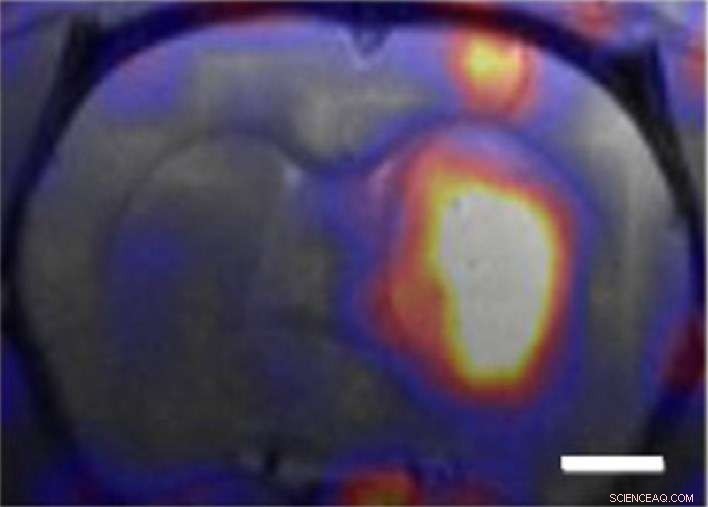

In a recent collaboration between Xu, Katherine Ferrara at the University of California (UC) Davis, and John Forsayeth and Krystof Bankiewicz of UC San Francisco, 3HM nanocarriers were tested on GBM tumors in rats. Using the radioactive form of copper (copper-64) in combination with positron emission tomography (PET) and magnetic resonance imaging (MRI), the collaboration demonstrated that 3HM can cross the blood brain barrier and accumulate inside GBM tumors at nearly double the concentration rate of current FDA-approved nanocarriers.

Copper-64 was used to label both 3HM and liposome nanocarriers for systematic PET and MRI studies to find out how a nanocarrier's size might affect the pharmacokinetics and biodistribution in rats with GBM tumors. The results not only confirmed the effectiveness of 3HM as GBM delivery vessels, they also suggest that PET and MRI imaging of nanoparticle distribution and tumor kinetics can be used to improve the future design of nanoparticles for GBM treatment.